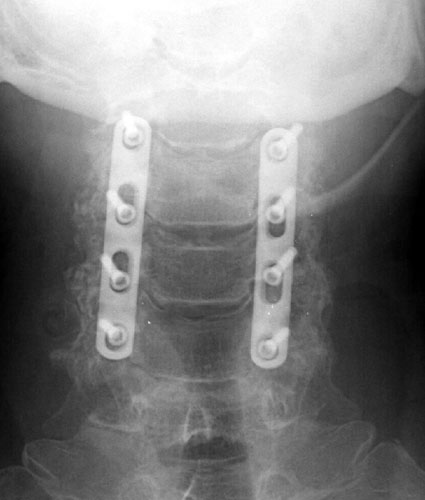

AP and lateral radiographs taken 5 days later, while still in the

hospital. Note migration of left C6 screw. It has loosened and fallen out. This

screw was not causing symptoms and decision was made to conservatively manage

the patient and keep in rigid cervical collar until the bone graft matured in

2-3 months. |